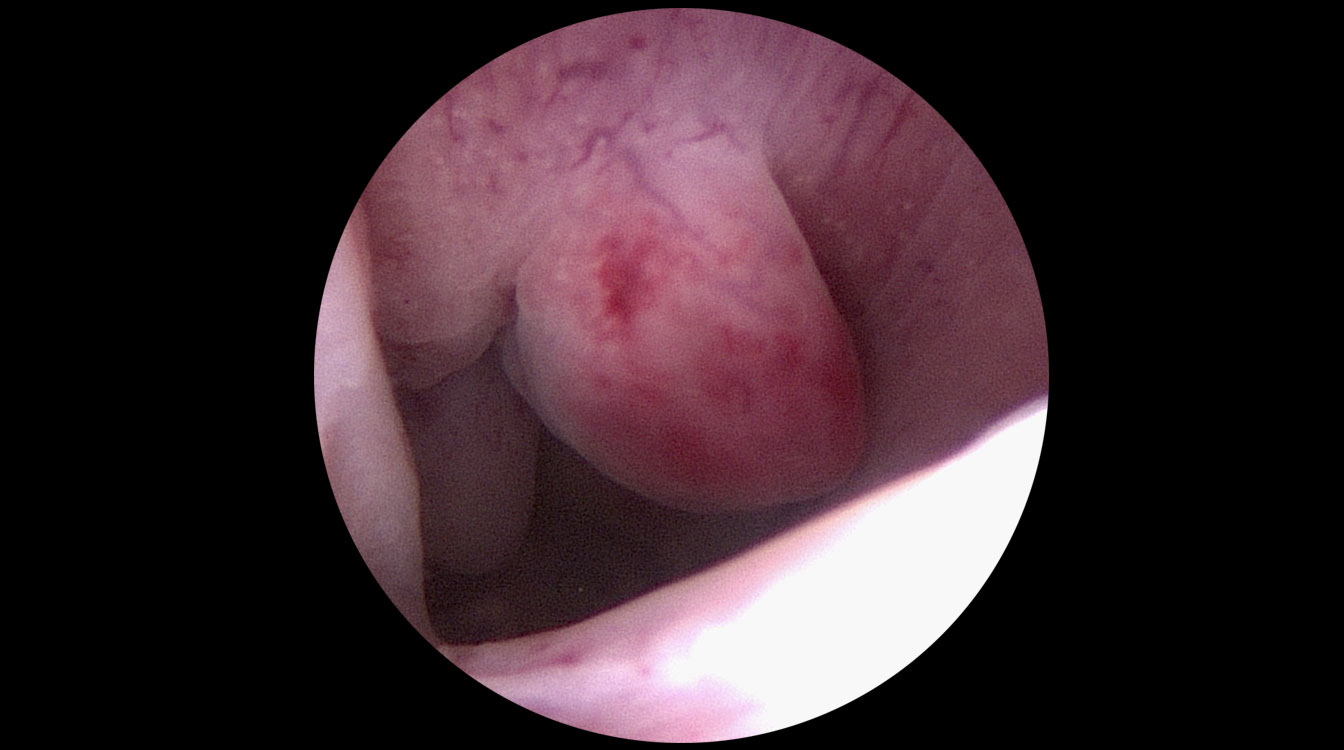

Astfel de fibroame sunt numite intracavitare sau submucoase. Prezența lor poate fi confirmată prin ecografie sau sonohisterografie (introducerea unei soluții saline intrauterine în timpul ecografiei) sau prin vizualizare directă cu un histeroscop (fig. 5).

Fibroamele pot fi rezecate în fragmente mici, cu ajutorul unor anse electrice în cadrul histeroscopiei, procedeu numit rezectoscopie (fig. 6). Fragmentele rezecate sunt colectate din cavitatea uterină și trimise la laboratorul de anatomie – patologică pentru diagnostic histologic. Cavitatea uterină are aspect normal după operație, crescând foarte mult probabilitatea unei sarcini reușite.